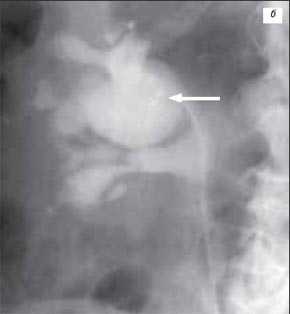

Рис. 3 (г-е). Псевдоопухоль гипертрофия Бертена (неполная "перемычка" паренхимы) в среднем отделе правой почки.

г) Эхограмма.

д) Экскреторная урограмма.

е) КТ с контрастным усилением.